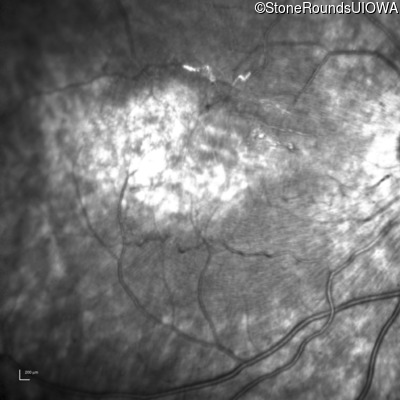

Infrared Fundus Photograph - Left - 20/200 +2

Exemplar